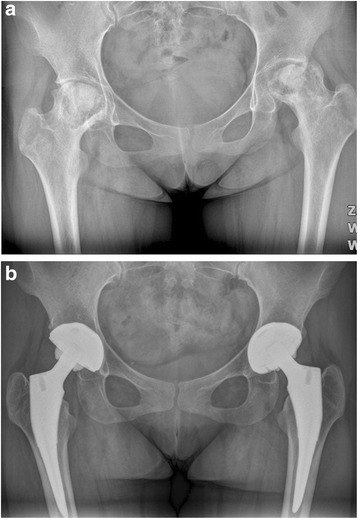

Fig. 1.

a A preoperative radiograph of the hip of a 75-year-old man who had femoral head osteonecrosis. b A radiograph at 28 months after implantation of short cementless femoral stem showed solid fixation in a satisfactory position

Fig. 2.

a A preoperative radiograph of the hip of a 73-year-old man who had femoral head osteonecrosis. b A radiograph at 28 months after implantation of conventional cementless femoral stem showed solid fixation in a satisfactory position